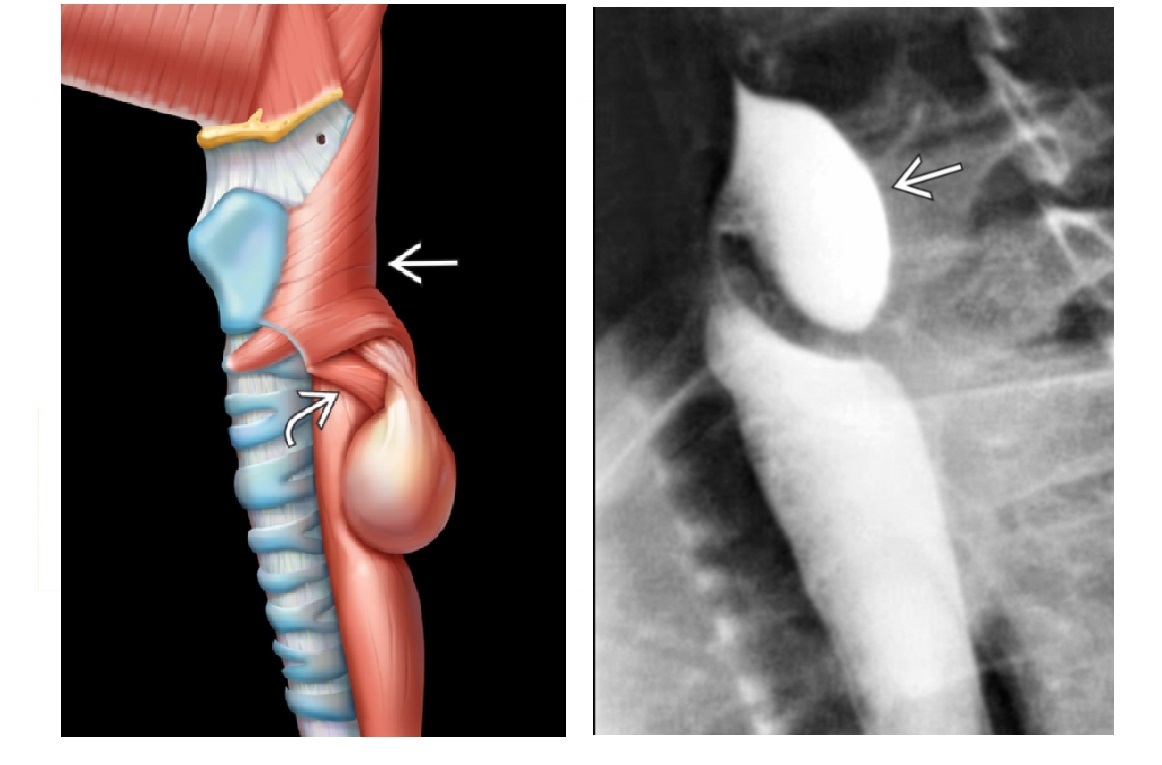

Zenker Diverticulum

Outpouching with rounded contour posteriorly in the neck is above the cricopharyngeus muscle

In hypopharynx!!!

Site of weakness is the Killian dehiscence - between the inferior pharyngeal constrictor muscle and cricopharyngeal muscle